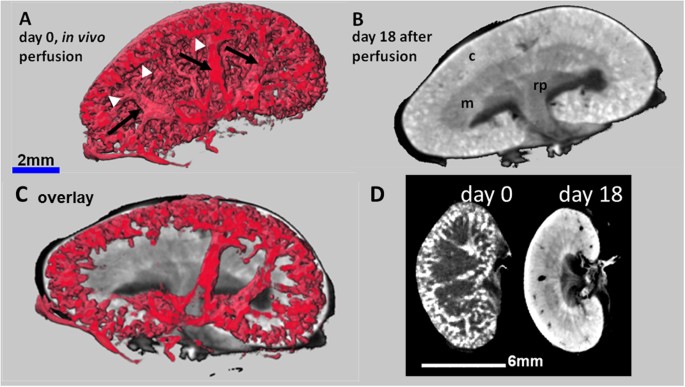

PTA perfusion followed by ex vivo PTA staining combines visualization of renal vascularization with morphological features

In order to increase the contrast of the supporting blood vessels in the kidney, mainly represented by the renal vein, the renal artery and their increasing number of branches towards the cortical periphery, we transcardially perfused mice with a 5% PTA solution before dissection and scanning by QuantumFX CT. Although the arteries and veins could not be clearly distinguished, a dense lattice of blood vessels from the segmental arteries and veins up to the small organisation grade of dense cortical arcuate vessels was depicted in detail ex vivo (Fig. 3A,D), approximately 20 min after PTA perfusion. To increase the morphological contrast, the kidneys were additionally immersed ex vivo in PTA solution according to the standard procedure for up to 18 days. While the long term diffusion of the PTA staining solution into the kidneys contrasted the renal cortex, medulla and renal pelvis, the perfused PTA solution within the vessels had completely leaked out (Fig. 3B,D). The composite image obtained by an overlay of the two 3D data sets with the software SCRY enabled the simultaneous depiction of the renal vessel lattices with their typical branching architecture and their underlying structural regions of renal cortex and medulla (Fig. 3C).

CT images of kidneys after in vivo PTA perfusion combined with ex vivo PTA staining. (A) Quantum CT scan of a kidney of a healthy mouse after in vivo PTA perfusion shows i) PTA filled blood vessels (arrows), bifurcated from the main renal vessels (not shown) to the arcuate vessels, and ii) the associated dense lattice of capillaries in the cortex in 3D (arrow heads). (B) In contrast, CT images of the same excised kidney after additional ex vivo PTA staining for 18 days visualizes the typical diffusion pattern, allowing the discrimination of anatomical structures such as cortex (c), medulla (m) and renal pelvis (rp). The vessel contrast is completely blurred. (C) An overlay of adjusted section planes of perfusion and diffusion data sets enables the co-localization of the blood vessels with the anatomical details of the kidneys. (D) 2D views of the same kidney at day 0 (kidney only perfused with PTA) and day 18 (kidney PTA perfused in vivo and PTA stained ex vivo) demonstrate the vessel contrast after PTA perfusion and the morphological contrast after PTA diffusion.